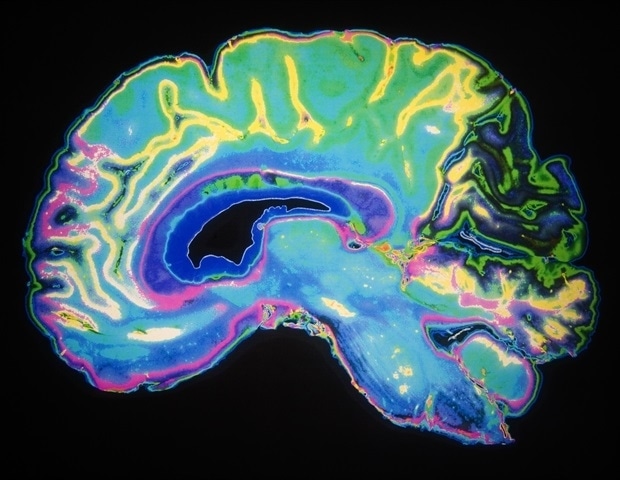

Η θεραπεία των εγκεφαλικών όγκων δεν είναι πάντα αποτελεσματική με τις συμβατικές μεθόδους. Μια ομάδα από την Empa, σε συνεργασία με το νοσοκομειακό δίκτυο HOCH Health Ostschweiz, εργάζεται για την ανάπτυξη νανοενζύμων, που μπορούν να επιτίθενται απευθείας στα καρκινικά κύτταρα κατά τη διάρκεια χειρουργικών επεμβάσεων. Ο εν λόγω εγχείρημα καταφέρνει να προχωρήσει χάρη στη γενναιόδωρη υποστήριξη διαφόρων ιδρυμάτων.

Η τρέχουσα διαδικασία περιλαμβάνει τη συνδυασμένη χρήση χειρουργικής επέμβασης, ακτινοθεραπείας και χημειοθεραπείας. Ωστόσο, η θέση του όγκου στον εγκέφαλο καθιστά την κατάσταση δύσκολη, εν μέρει λόγω του φράγματος αίματος-εγκεφάλου, που προστατεύει το όργανο από βλαβερές ουσίες αλλά και εμποδίζει κάποιες θεραπείες να εισέλθουν στον εγκέφαλο.

Ο ερευνητής Giacomo Reina και η ομάδα του στο εργαστήριο Νανοϋλικών Υγειάς επιδιώκουν να παρακάμψουν αυτό το φράγμα μέσω έξυπνης προσέγγισης: αναπτύσσουν βιοσυμβατά νανοϋλικά που θα χρησιμοποιούνται κατά τη διάρκεια της χειρουργικής επέμβασης. “Δεδομένου ότι τα καρκινικά κύτταρα έχουν ιδιαίτερα ενεργό μεταβολισμό, τα φάρμακα συσσωρεύονται συγκεκριμένα στον ιστό του όγκου,” λέει ο Reina. Παράλληλα, τα νανοενζυμα μπορούν να ενεργοποιηθούν με κοντόφασμα υπέρυθρο φως, προσφέροντας έναν ακριβή και ελεγχόμενο τρόπο δράσης.